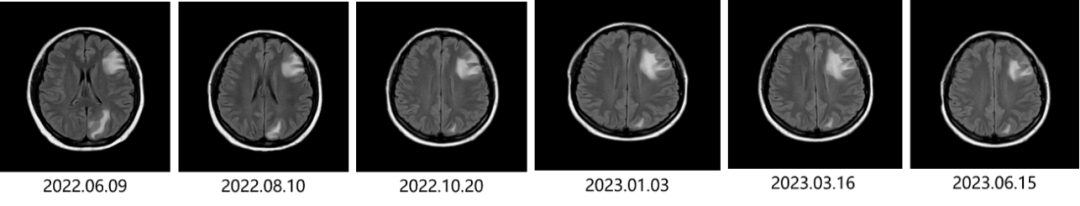

• 2022.04.29开始行T-DM1方案治疗。定期复查,肝脏病灶持续缩小;颅内转移灶略缩小,控制稳定;骨转移灶控制稳定。治疗过程中发生≤2级血小板减少,对症给予海曲泊帕升血小板治疗,后血小板恢复正常。

• 2022.04.29 肝脏超声提示转移灶约3.6cm*2.2cm;2022.06.09 肝脏超声提示转移灶约3.1cm*2.0cm。

• 2023.06.15 患者颅内病灶稳定,肝脏转移灶消失,骨转移灶稳定。

图1 T-DM1治疗肝转移灶变化